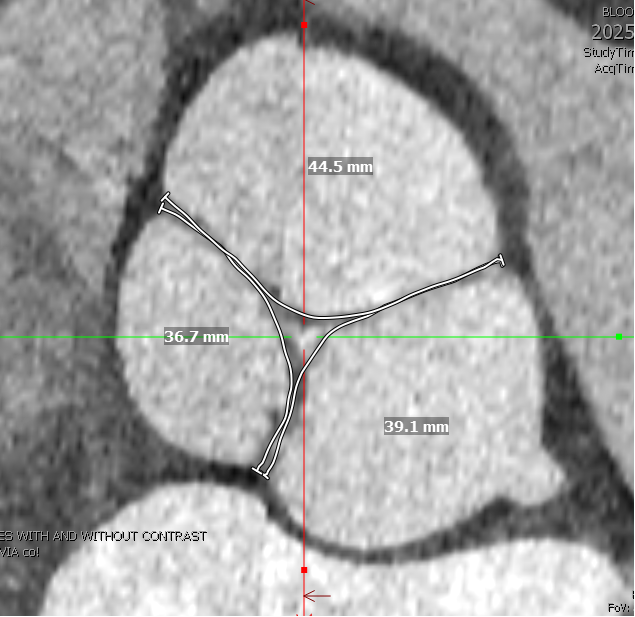

Our newest @JAHA_AHA review on the #RossProcedure is out today... a surgeon/cardiologist collaboration offering a modern look at patient selection, surgical technique, and long-term outcomes to guide practice.